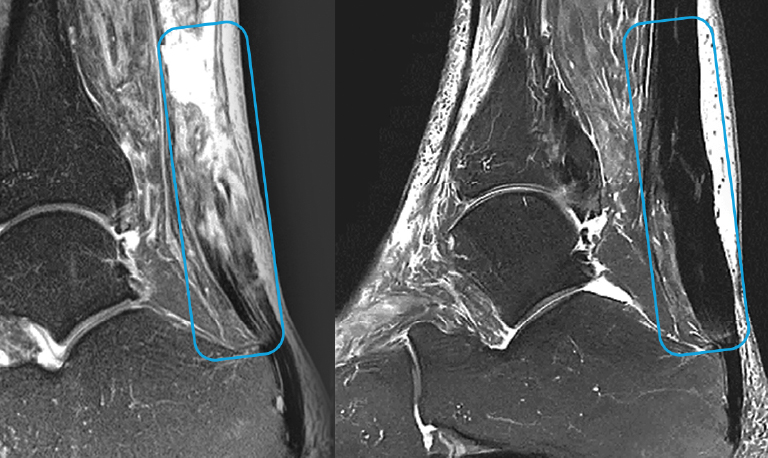

Lesiones de tendónLas CMC aplicadas por vía intratendinosa han demostrado regeneración estructural en tendón rotuliano, de Aquiles, isquiotibiales y supraespinoso, con validación mediante resonancia magnética y mejora funcional sostenida.

El tratamiento incluye no solo la aplicación del medicamento, sino un seguimiento clínico individualizado que puede extenderse entre 2 y 5 años, dependiendo de la patología. Durante este periodo se realizan controles funcionales y estructurales periódicos, que incluyen pruebas de imagen como resonancia magnética, con el objetivo de evaluar la evolución clínica del paciente, la estabilidad del efecto biológico y la seguridad a largo plazo.